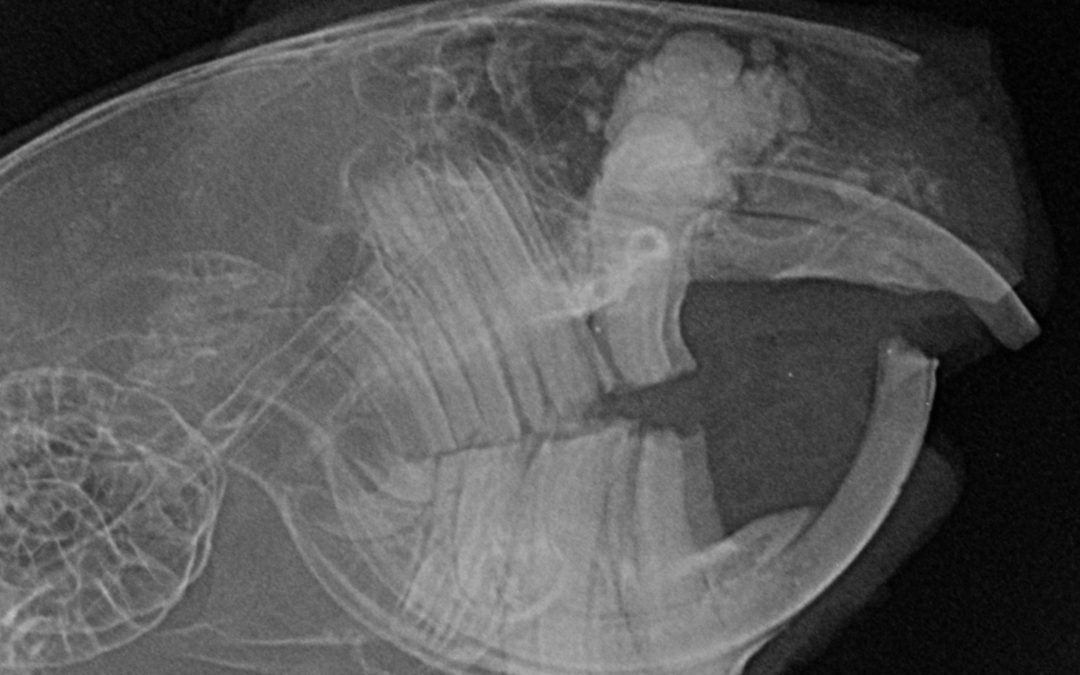

Das Titelfoto zeigt ein Nagetier. Es schnupfte, die Zähne mussten regelmäßig gekürzt werden. Das Röntgenbild zeigt, daß die Ursache für den Problemkomplex ein Tumor oder eine sehr massive Entzündung war.